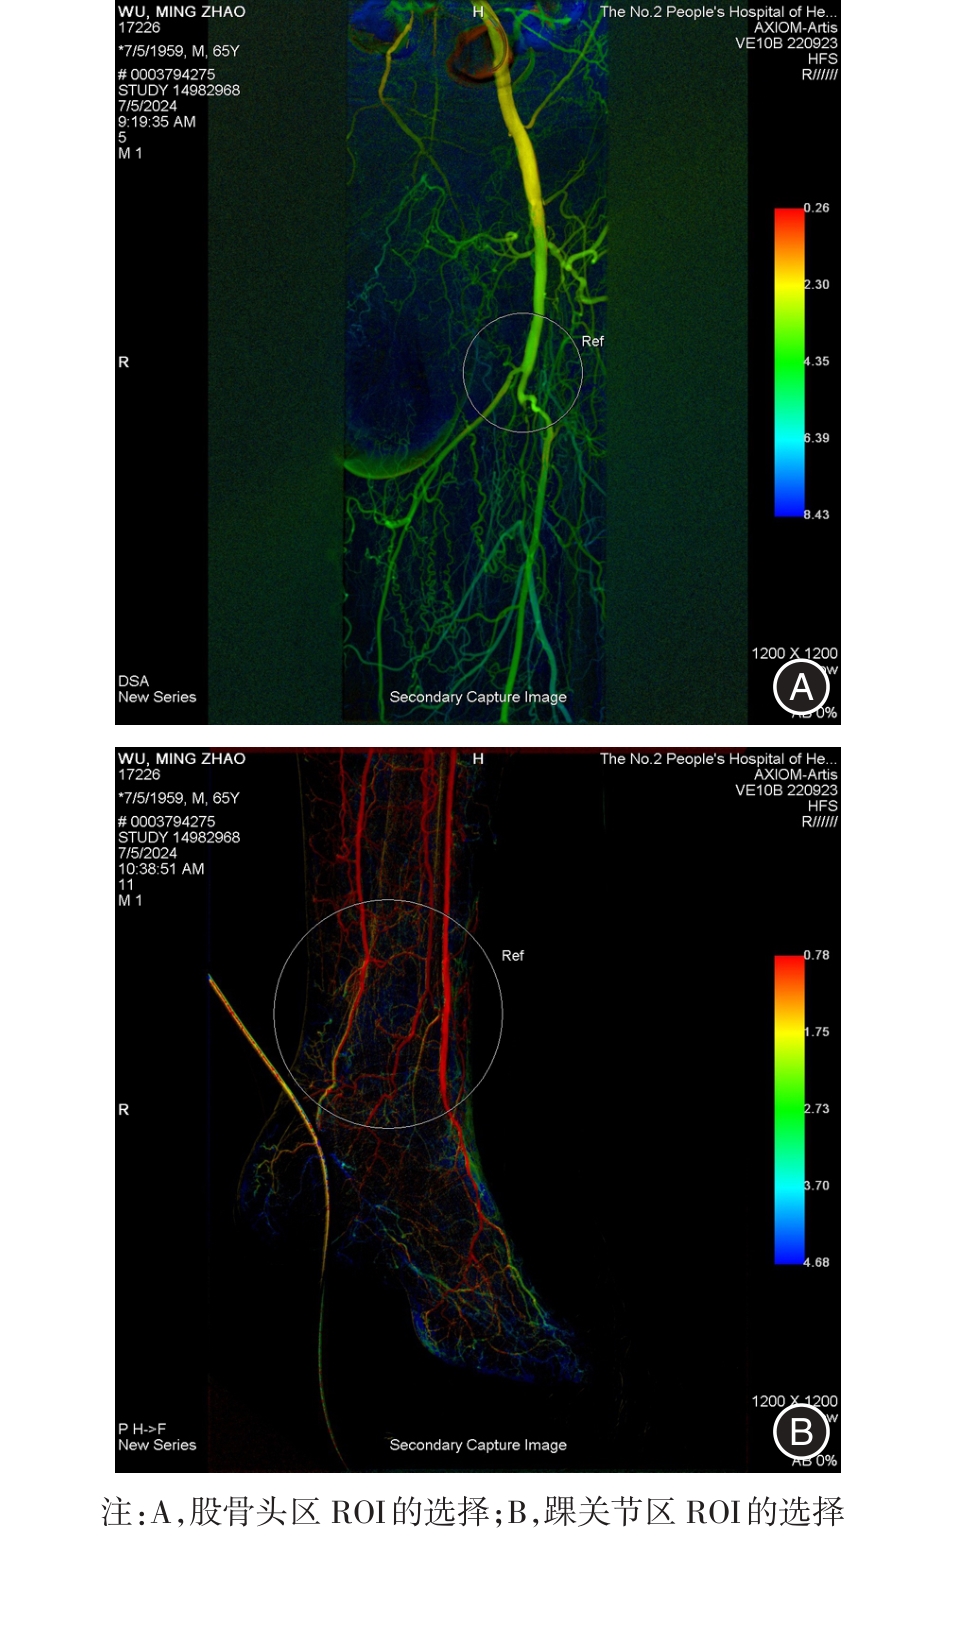

目的 研究iFlow彩色血流编码成像技术在下肢动脉硬化闭塞症(LEASO)诊断中的应用价值。 方法 选择2022年3月至2023年10月期间确诊的106例LEASO患者作为本研究的LEASO组,以一般资料与LEASO组匹配且无动脉病变的80例志愿者作为对照组。两组受试者均进行数字减影血管造影(DSA)并采用iFlow彩色血流编码成像技术检测股骨头区域和踝关节区域达峰时间(TTP)、计算踝关节区域与股骨头区域 TTP的差值,测量踝肱指数(ABI)。 结果 两组研究对象年龄、性别、体质量指数、吸烟史、高血压病史、糖尿病史、冠心病史、股骨头区域TTP的比较,差异无统计学意义(P > 0.05);LEASO组踝关节区域TTP及TTP差值均高于对照组,差异有统计学意义(P < 0.05);LEASO组中不同Rutherford分类患者股骨头区域TTP的比较以及左侧病变患者与右侧病变患者股骨头区域TTP、踝关节区域TTP、TTP差值的比较,差异无统计学意义(P > 0.05),Rutherford分类越高,踝关节区域TTP及TTP差值越低(P < 0.05);经Pearson检验,LEASO患者的踝关节区域TTP、TTP差值与ABI呈负相关(P < 0.05);经受试者工作特征(ROC)曲线分析,踝关节区域TTP、TTP差值对LEASO具有诊断效能;经Delong检验,TTP差值诊断的ROC曲线下面积高于踝关节区域TTP(P < 0.05)。 结论 iFlow彩色血流编码成像技术测定踝关节区TTP及TTP差值是诊断LEASO的量化指标。

Objective To investigate the clinical utility of iFlow color flow coding imaging technology in the diagnosis of lower extremity arteriosclerosis obliterans (LEASO). Methods A total of 106 patients diagnosed with LEASO between March 2022 and October 2023 were included as the LEASO group, while 80 volunteers without arterial disease but matched with LEASO were selected as the control group. Both groups underwent digital subtraction angiography (DSA), and iFlow color flow coding imaging technology was employed to assess time to peak (TTP) in the femoral head and ankle regions. The difference value of TTP between these two regions was calculated, along with measurement of ankle-brachial index (ABI). Results There were no significant differences in age, sex, body mass index, smoking history, hypertension history, diabetes history, coronary heart disease history and TTP in the femoral head between the two groups (P > 0.05). However, the TTP in the ankle area and the difference values of TTP in the LEASO group were significantly higher than those in the control group (P < 0.05). The comparison of TTP in the femoral head region among patients with different Rutherford classifications and between patients with left and right lesions in the LEASO group showed no statistical significance (P > 0.05). Furthermore, a negative correlation was observed between Rutherford classification and both TTP values in ankle joint region as well as TTP difference value (P < 0.05), indicating that higher Rutherford classification is associated with lower TTP values. Pearson test results revealed a significant negative correlation between TTP values and ankle joint region/TTP difference value of LEASO patients with ABI ( P < 0.05). Receiver operating characteristic curve analysis demonstrated that both TTP values in ankle joint region and TTP difference value are effective diagnostic indicators for LEASO; moreover, Delong test indicated that area under ROC curve for TTP difference value was significantly higher than that for TTP value alone (P < 0.05) Conclusion iFlow color flow coding imaging technology enables quantitative assessment of both TPP values within ankle joint region as well as their differences which can be utilized for diagnosis of LEASO.